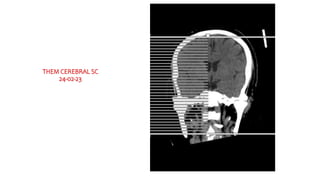

THEM CEREBRAL SC

24-02-23